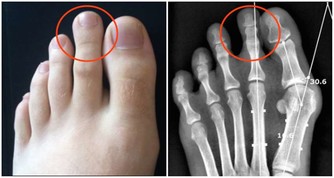

現代人飲食五花八門,容易營養過剩,大家普遍會認為胖不好!但高齡醫學專家表示,「體重稍微肥胖」者(BMI值23-25間)其實死亡率比較低,體重過輕的人因為營養失調,一旦染病就容易有併發症。稍微胖一點,才有本錢對抗疾病,不須太忌口,只要維持好飲食習慣,避免三高(高血壓、高血糖、高血脂)就可以。

圖片來源:tieba.baidu.com(圖為示意圖)不管外表看起來胖還是瘦,健康才是最重要的~ 分享出去讓朋友也知道吧!